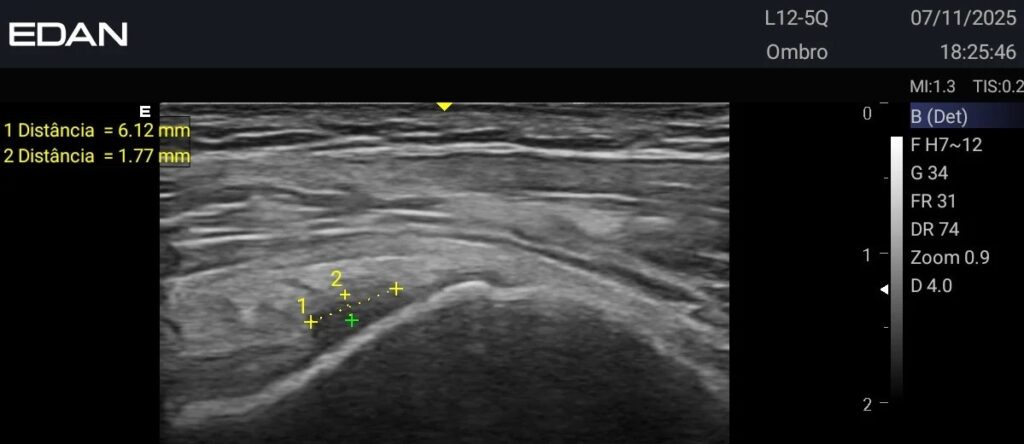

imagem de ultrassonografia do ax3

Entre os destaques do mercado, a linha de ultrassom AX da Edan, especialmente o modelo AX3, se sobressai ao combinar alta performance com portabilidade e recursos avançados de imagem. Esses equipamentos são ideais para clínicas e hospitais que buscam eficiência, precisão e agilidade, oferecendo suporte tanto para exames de rotina quanto para contextos críticos, como emergências e procedimentos guiados por imagem.